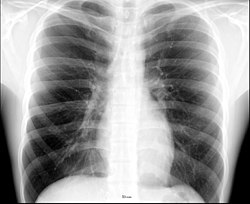

При изучении рентгеноанатомии органов грудной клетки обращают внимание на рентгеновскую структуру видимых костей и мягких тканей грудной клетки; форму и прозрачность для рентгеновских лучей областей, на которые проецируется лёгочная ткань (так называемых «лёгочных полей»), а также их структуру, сформированную тенями сосудов лёгких («лёгочный рисунок»); расположение и структурность корней лёгких; положение, форму куполов диафрагмы и синусов плевральных полостей; форму и размеры тени средостения (в том числе сердца).

Лёгкие на рентгенограмме образуют лёгочные поля, располагающиеся по обе стороны от интенсивной тени средостения. Правое лёгочное поле короче и шире левого. В лёгочных полях различают верхушки (зоны выше ключиц), верхние отделы — от верхушек до передних отрезков вторых рёбер, средние отделы — между вторыми и четвёртыми парами рёбер, и нижние отделы — от четвёртых рёбер до диафрагмы. Лёгочные поля в норме очень светлые (тёмные на негативе) из-за высокой рентгенопроницаемости заполненной воздухом лёгочной ткани. Структура лёгочных полей называется лёгочным рисунком, анатомическим субстратом которого являются лёгочные сосуды и, в малой степени, лёгочный интерстиций. Лёгочный рисунок визуализируется в виде переплетения сосудистых теней тяжистого, округлого и овального вида, более интенсивных в местах их пересечений. В направлении от корней лёгких к периферии рисунок лёгочных сосудов становится беднее и совсем не визуализируется на расстоянии 1—1,5 см от края лёгочных полей. Лёгочный рисунок наиболее густой в нижних отделах лёгочных полей, обедняясь к верхушкам. Тени бронхов на рентгенограмме визуализируется в виде двойных полосок или колец с просветлением внутри.[3][4]

Сердечно-сосудистая тень занимает центральное положение на рентгенограмме органов грудной клетки. На рентгенограмме в прямой проекции её контуры в норме формируют две дуги справа и четыре — слева. Нижняя дуга правого контура образована правым предсердием, верхняя, более медиальная — восходящей частью аорты и верхней полой веной. Первая (верхняя) левая дуга образована дугой и начальным отделом нисходящей аорты, вторая — лёгочным стволом, третья — ушком левого предсердия, четвёртая — левым желудочком. В области второй и третьей дуг контур тени средостения вогнут и носит на этом уровне название «талия сердца»; эта зона является границей между сердцем и связанными с ним сосудами.[5]